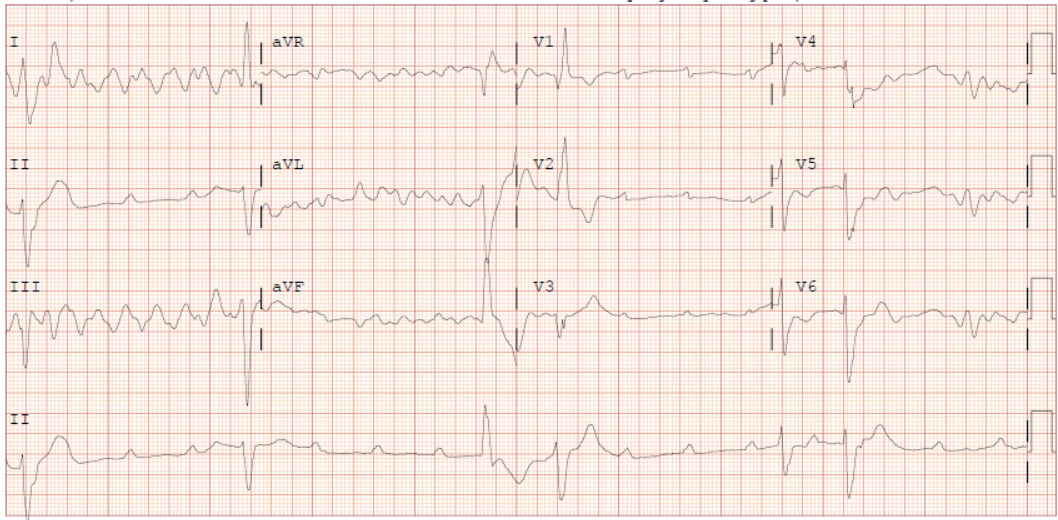

A 62-year-old male with a past medical history notable for left nephrectomy and recent complete heart block status post dual-chamber pacemaker insertion (Figures 1A and 1B) presented with right-sided pectoralis major twitching and persistent singultus. Symptoms began insidiously on post-procedure day five, and after two days of persistent singultus, the patient presented to the hospital. Vital signs were stable, and physical examination revealed ongoing singultus, visible rhythmic contractions of the right chest wall, and no signs of infection at the insertion site or clinical signs of overt heart failure. He denied cough, fever, chest discomfort, shortness of breath, inducible fasciculations, or extremity hypertonia. An electrocardiogram (Figure 1C) demonstrated a paced rhythm consistent with atrioventricular sequential pacing; however, an immediate repeat electrocardiogram (Figure 1D) revealed atrial dissociation with ventricular pacing.